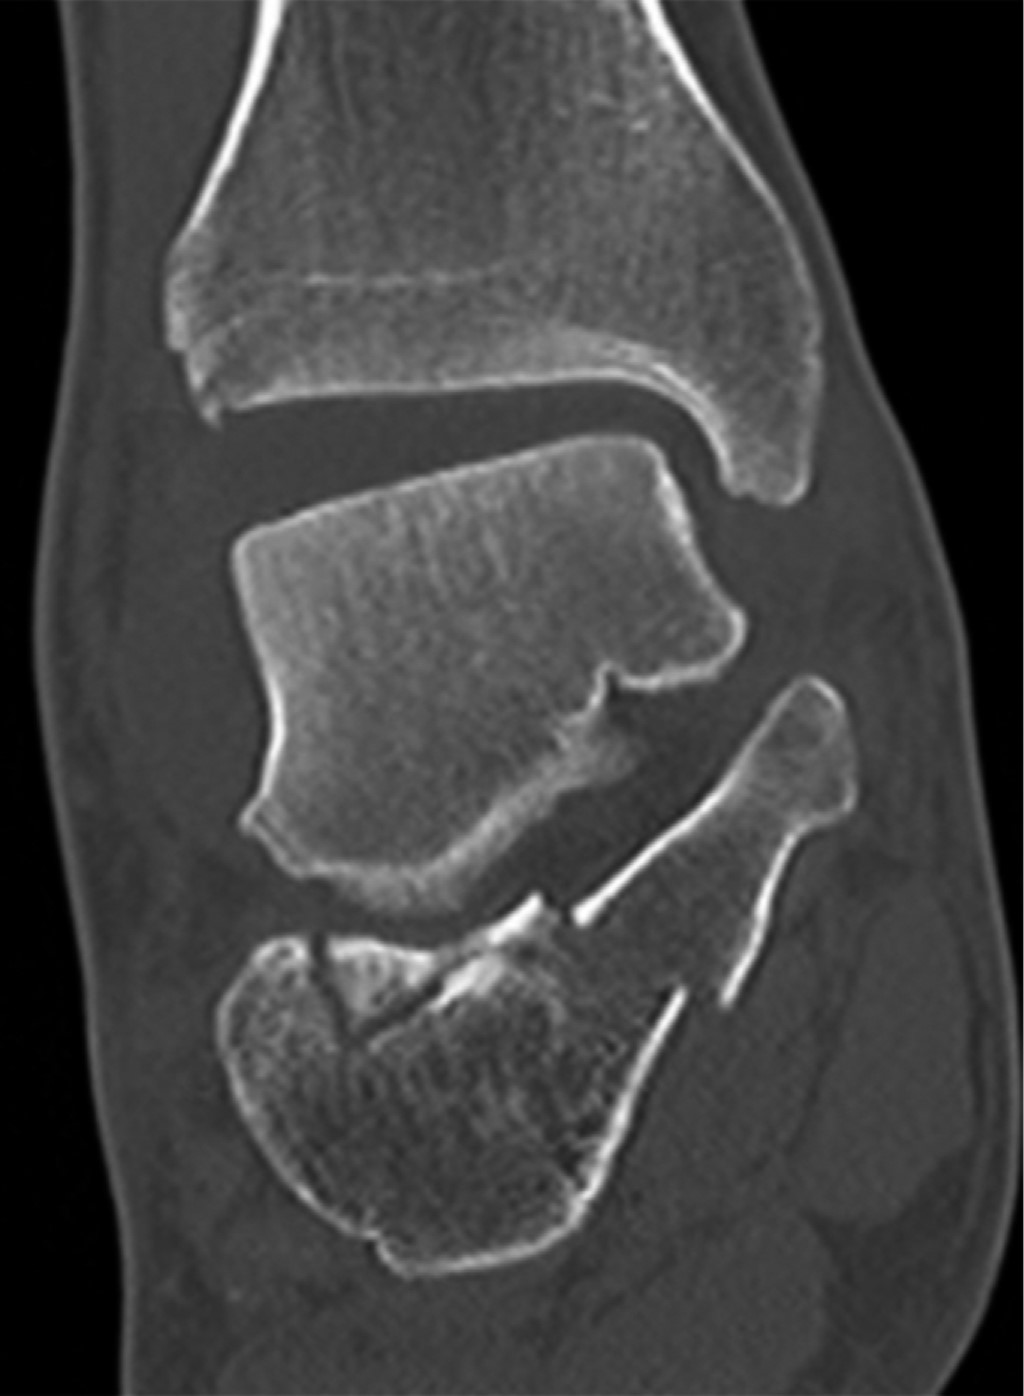

Paciente masculino de 39 años de edad, sin antecedentes de relevancia, sufre traumatismo de moderada energía en miembro inferior derecho. Relató entorsis de tobillo asociado a trauma directo en talón. Presentaba dolor, edema, hematoma e impotencia funcional. El examen físico reveló inestabilidad ante la maniobra de flexión plantar e inversión. Las radiografías evidenciaron fractura de calcáneo desplazada, con marcada alteración de los ángulos de Bohler (-8o) y Gissane (116o) (Figura 1). La tomografía evidenció compromiso de la articulación subastragalina y alteración de la articulación tibioperoneo astragalino 3AC según la clasificación de Sanders6 (Figura 2). Se realizó inmovilización con bota corta de yeso.

Figura 3